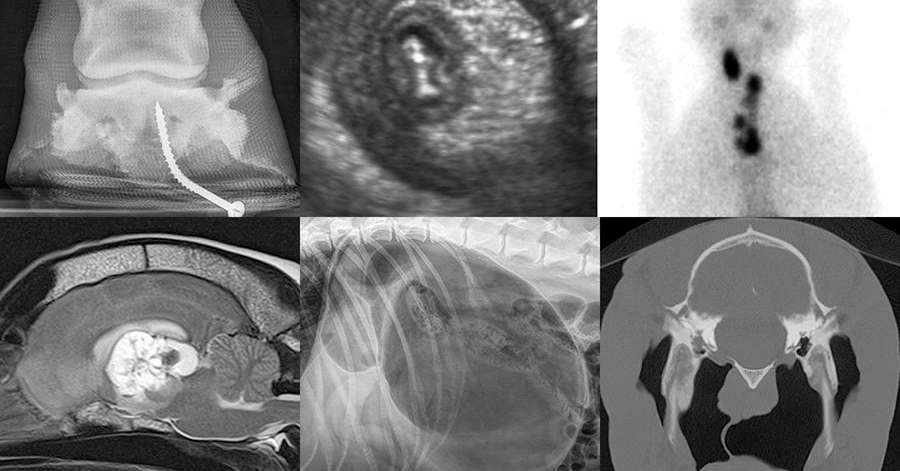

Diagnostic Imaging Technology X Ray Ct And Mri Scans